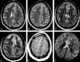

Autosomal Dominant Retinal Vasculopathy with Cerebral Leukodystrophy (AD-RVCL) (previously known also as Cerebroretinal Vasculopathy, CRV, or Hereditary Vascular Retinopathy, HVR or Hereditary Endotheliopathy, Retinopathy, Nephropathy, and Stroke, HERNS) is an inherited condition resulting from a frameshift mutation to the TREX1 gene. This genetically inherited condition affects the retina and the white matter of the central nervous system, resulting in vision loss, lacunar strokes and ultimately dementia. [Source: Wikipedia ]